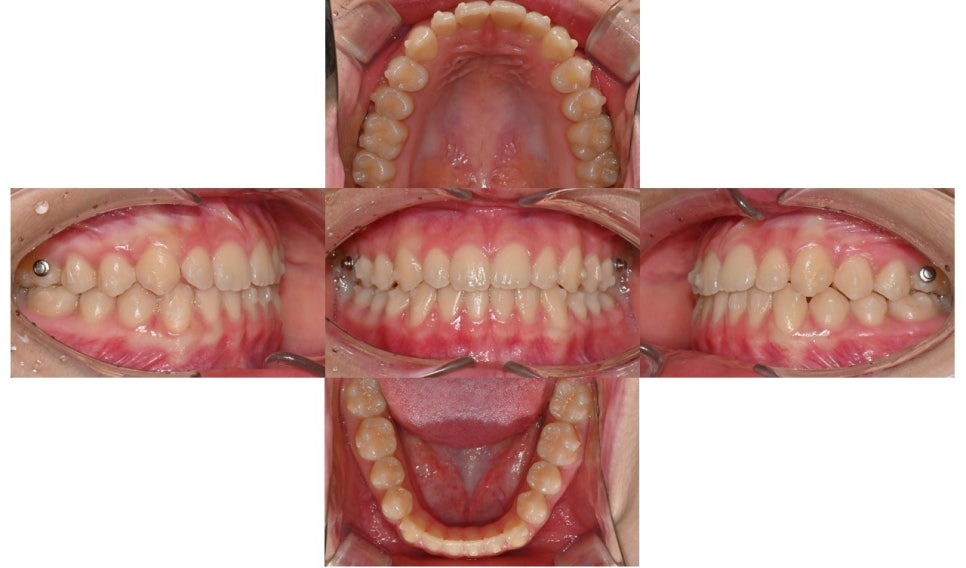

치료 시작 6개월 후 사진으로 아래 앞니 공간은 거의 닫혔으며 4달 전에 비해 어금니 교합도 많이 개선되었습니다. 아직 위아래 앞니 중심선은 일치하지 않습니다.

치료 시작 6개월 후

치료 시작 8개월 후 사진으로 치아 사이에 벌어졌던 공간은 거의 다 닫혔으며 어금니 교합도 개선되었습니다. 위아래 치아 중심선도 일치하고 있습니다. 현재 미세하게 치아 위치 조정하며 마무리 중입니다.

치료 시작 8개월 후